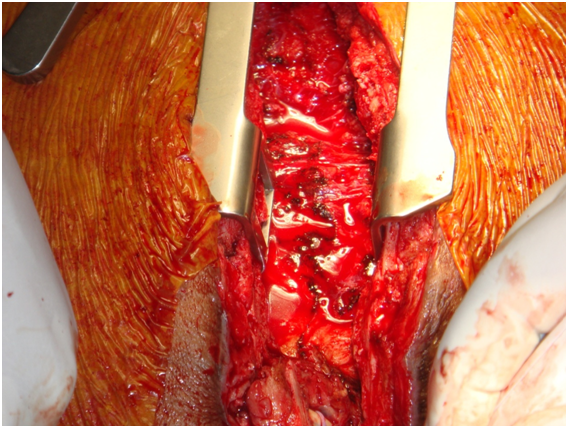

Chest incision was very technical-started from below with oscillator saw upto upper 1/3rd of sternum near aneurysm. Now upper part from above-near aneurysm curved the saw to right avoiding the aneurysm, put small retractor now gradually cut through bony surface so not went into graft and go around aneurysm without rupturing it but suddenly aneurysn came to leak--now no way--gentle pressure on leak and proceeded for total circulatory arrest. During going to total circulatory arrest, dissection around heart was done through diaphragmatic surface and right side. Now at 180C total circulatory arrest was done, taken out graft, found oval shaped opening at ascending aorta, a Dacron patch taken and covered it by continuous proline suture.

Figure 8: Oval shape opening at ascending aorta, a Dacron patch taken and covered it by continuous proline suture.

Figure 9: Oval shape opening at ascending aorta, a Dacron patch taken and covered it by continuous proline suture.